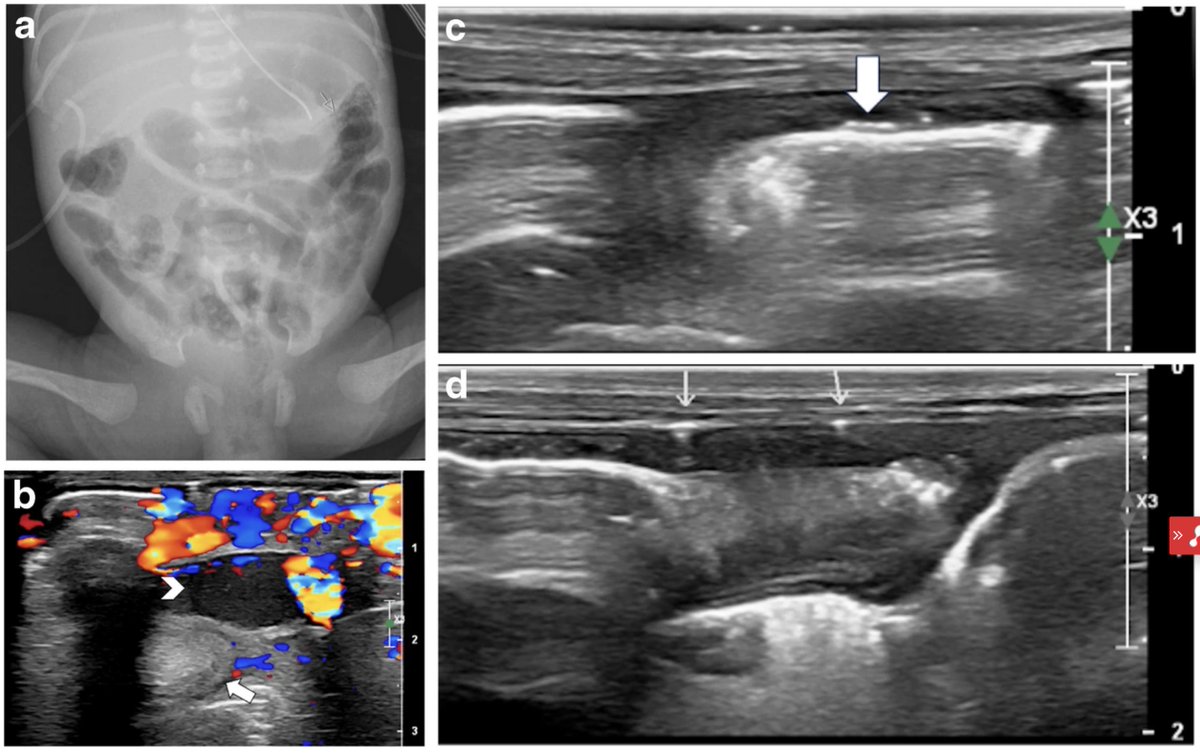

Adjunct abdominal USS for #NEC at time of initial diagnosis 7/23 USS -> findings of NEC when initial AXR unremarkable Sensitivity aUSS for NEC 0.91 59% aUSS -> higher Bell stage Implementing standardized aUSS guideline feasible & may aid NEC diagnosis https://t.co/hVtpFepHJG